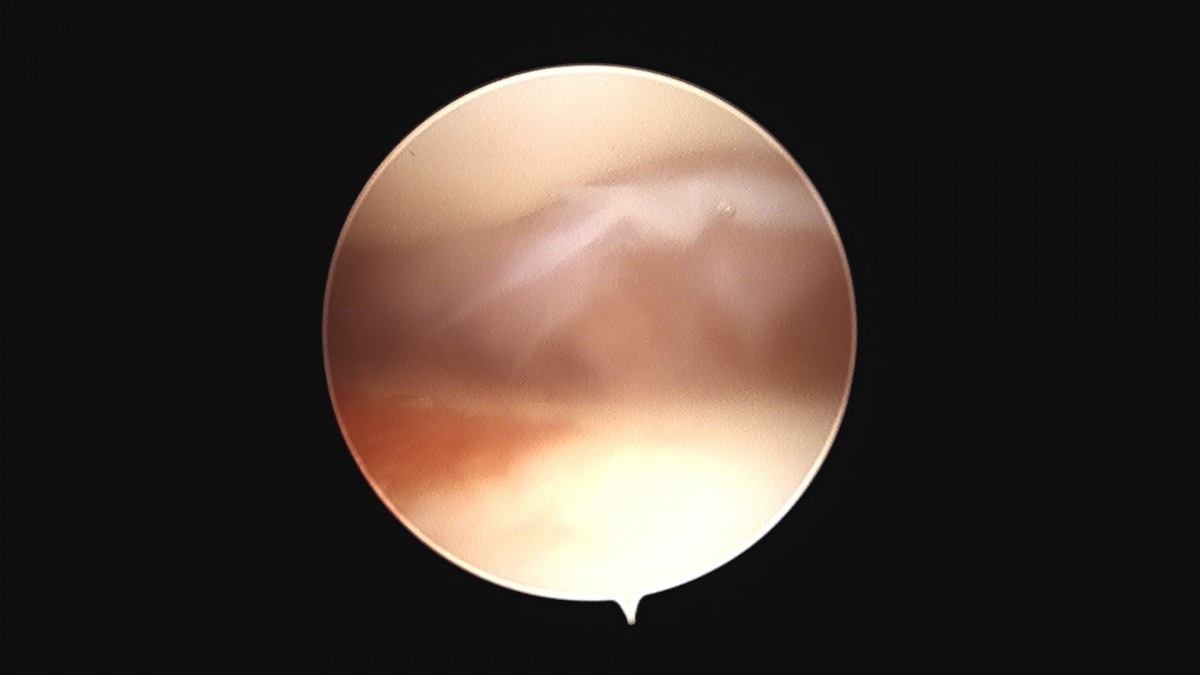

이재상원장님 무릎 변연절제술 권오O 환자

작성자 최고관리자 댓글 0건 조회 373회 작성일 25-09-16 16:11